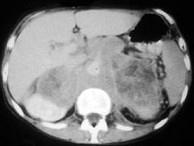

问题 男,76岁,全身浅表淋巴结肿大,请结合下列图片作出诊断 ( )

选项 A、肾上腺转移瘤 B、肾上腺淋巴瘤 C、肾上腺癌 D、肾上腺嗜铬细胞瘤 E、肾上腺腺瘤

答案 B